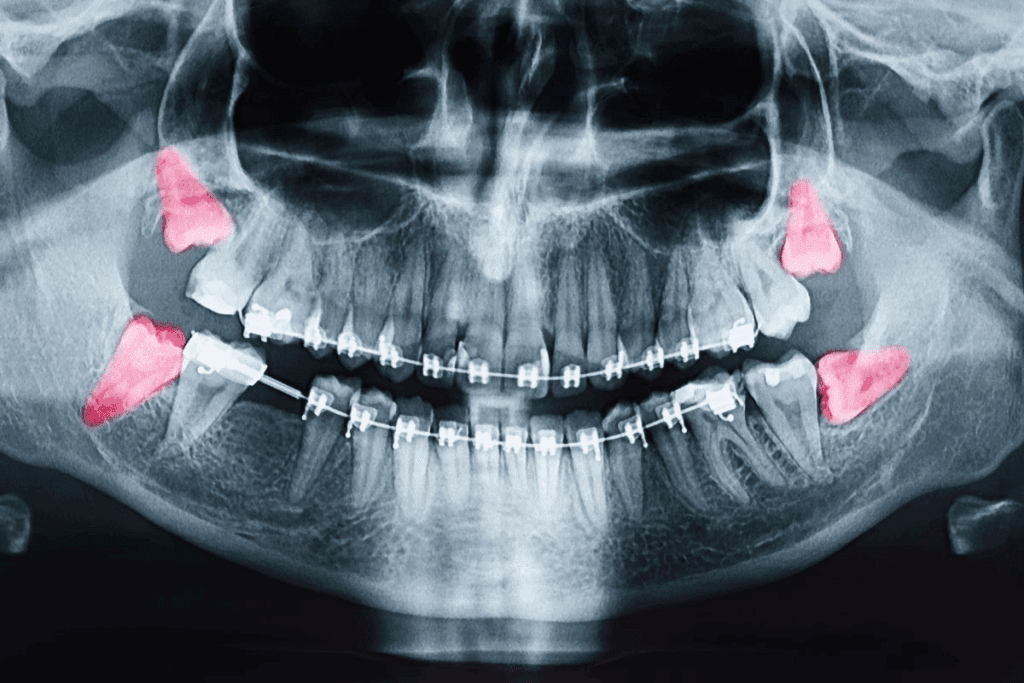

Dental Issues Causing Right-Side Jaw Pain

Dental problems often lead to right-side jaw pain. Issues like tooth infections, abscesses, and TMJ disorders can cause this pain. It’s important to know the causes and get dental help to treat and prevent more problems.

Can dental issues cause right-side jaw pain, and if so, how?

Yes, dental problems like tooth infections and abscesses can cause jaw pain. Impacted wisdom teeth also refer pain to the jaw area.